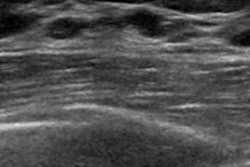

The picket fence sign is seen when many closely spaced Cooper’s ligaments are involved in cancer, creating a shadowing area resembling a picket fence profile. The Golden Gate sign occurs when two or three adjacent Cooper’s ligaments are affected by cancer, creating a hypoechoic area resembling a suspension bridge in profile.